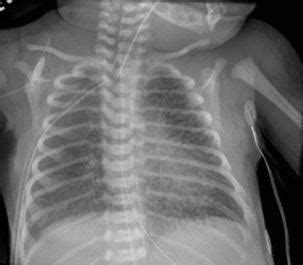

Alright, let’s get into the nitty-gritty of what Pulmonary Interstitial Emphysema (PIE) actually is . Imagine your lungs as a bunch of tiny balloons, right? These are your alveoli, where the magic of gas exchange happens – oxygen in, carbon dioxide out. Now, surrounding these balloons is a delicate framework, a sort of support structure made of connective tissues and small blood vessels. This framework is what we call the interstitium. In PIE, something goes wrong, and air, instead of just staying within the alveoli, starts to leak out and collect in this interstitial space. Think of it like a slow leak in a balloon that starts to inflate the area around the balloon, rather than just the balloon itself. This trapped air can then compress the tiny airways and blood vessels, making it harder for air to flow in and out of the lungs and for oxygen to get into the bloodstream. This compression and stiffening is what causes the breathing difficulties associated with PIE. It’s a bit like trying to breathe through a straw that’s been squeezed – not easy!

One of the key distinctions of PIE is its common association with infants , especially premature babies who have undergone mechanical ventilation. Their lungs are still developing and are incredibly fragile. When they need help breathing, the positive pressure from ventilators, while life-saving, can sometimes force air into the interstitial spaces if there are tiny tears or weaknesses. This is often referred to as acquired PIE in neonates. However, PIE isn’t exclusive to newborns. It can also occur in adults, although it’s much rarer. In adults, it’s often linked to underlying lung diseases like cystic fibrosis, or it can be a complication following lung transplantation or certain types of lung surgery. The core issue remains the same: air escaping its normal pathways and accumulating where it shouldn’t be, leading to compromised lung function. So, while the underlying cause might differ, the effect on the lungs is a shared pathway of damage and difficulty breathing.

So, what exactly causes this sneaky condition, Pulmonary Interstitial Emphysema ? The primary culprits often depend on whether we’re talking about babies or adults. In neonates , particularly premature infants, the main driver is often the need for mechanical ventilation . Premature lungs are underdeveloped, with weaker alveolar walls. When a baby is on a ventilator, the machine provides breaths with positive pressure. While essential for survival, this pressure can sometimes be too much for these delicate lungs, forcing air to dissect through the lung tissue into the interstitial spaces. This is especially true if the baby also has other lung conditions like respiratory distress syndrome (RDS) or meconium aspiration syndrome, which can further weaken the lung structure. It’s a bit of a Catch-22 situation – the life support can, in some instances, contribute to the problem.

Spotting Pulmonary Interstitial Emphysema (PIE) isn’t always straightforward, as the symptoms can mimic other respiratory issues, especially in infants. However, doctors are trained to look for specific clues. In newborns , persistent respiratory distress that doesn’t improve with standard treatments is a major red flag. This can manifest as rapid breathing (tachypnea), grunting sounds with each breath, nasal flaring, and a bluish tint to the skin (cyanosis) due to low oxygen levels. You might also notice that the baby’s chest seems unusually distended or